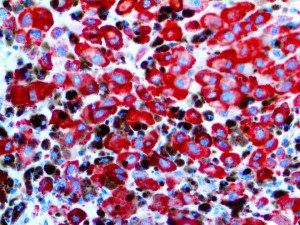

It is the ICU physician who is most likely to witness one of the deadliest manifestations of the abnormal immunological response, the cytokine storm syndrome (CSS). This response is also referred to by some as the cytokine release syndrome (CRS). CSS is characterized by continuous activation and expansion of macrophage and lymphocyte populations, which secrete large amounts of cytokines, causing the cytokine storm. This massive cytokine release is akin to hemophagocytic lymphohistiocytosis (HLH) disease, a syndrome characterized by initial unchecked and persistent activation of cytotoxic T lymphocytes and NK cells.

Clinical and laboratory manifestations of HLH include fever, enlarged liver and/or spleen, neurologic dysfunction, coagulopathy, liver dysfunction, cytopenias (i.e., low levels of erythrocytes, leukocytes, and/or platelets), hypertriglyceridemia, hyperferritinemia, hemophagocytosis, and eventually diminished NK cell activity as the immune system becomes progressively paralyzed. HLH can be familial (primary HLH) or secondary to another disease process (sHLH), such as rheumatic disease, in which it is referred to as macrophage activation syndrome (MAS, characterized by elevated ferritin).